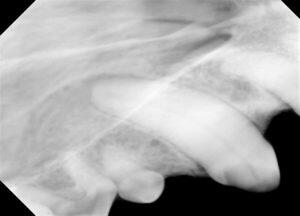

1.右側外観です。

2.露髄を伴う歯冠破折です。